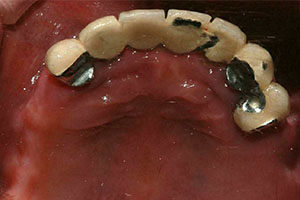

치료증례 전후사진

Before & After